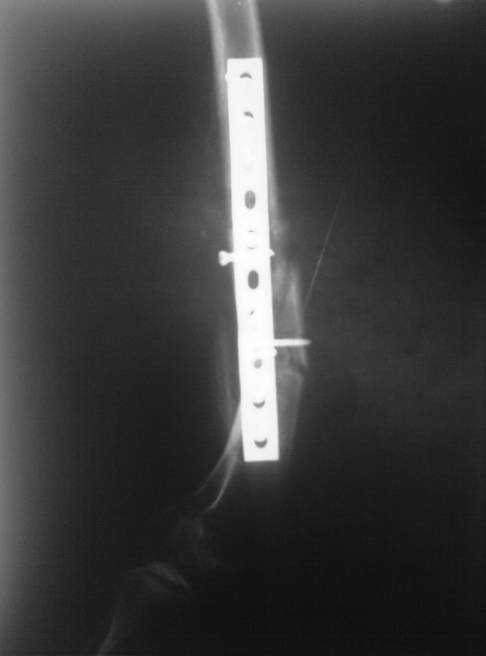

В мае 2007 года оперирована в Уральском НИИТО г. Екатеринбурга. Выполнено: полузакрытое удаление пластины и винтов, IM блокируемый остеосинтез.

На сегодняшний момент (2 месяца после операции). Больная передвигается при помощи трости из-за чувства неуверенности и ощущения онемения в подколенной ямке. В квартире передвигается без дополнительной опоры. Снимки в аттаче.

Вроде все на месте, и периостальные напластования были и до штифтования...